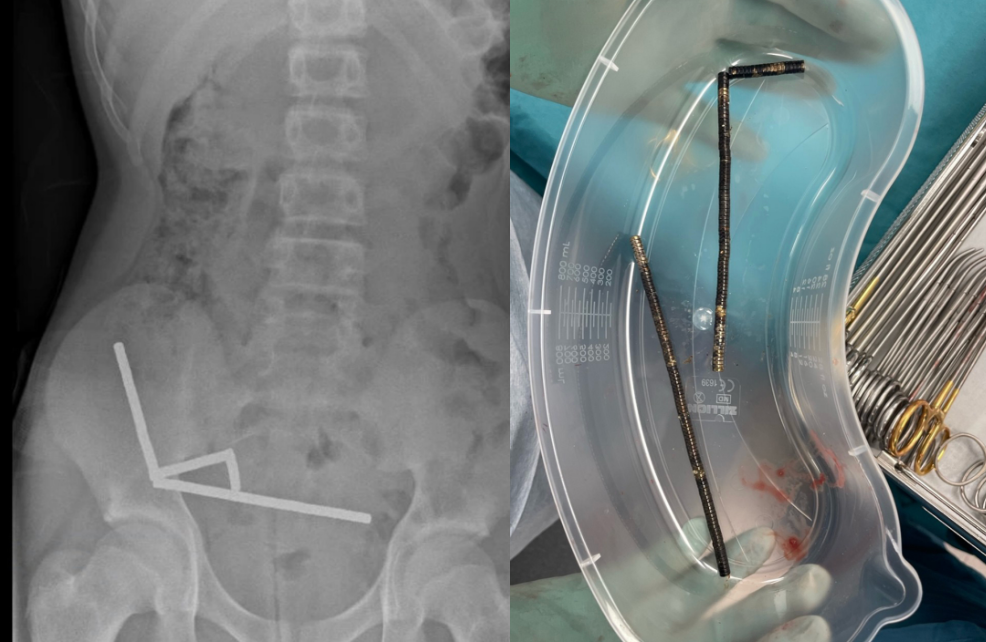

An X-ray shows lines of magnets in the boy's abdomen.  / Credit: New Zealand Medical Journal

An X-ray shows lines of magnets in the boy’s abdomen. / Credit: New Zealand Medical Journal

Scans showed that the magnets had linked into four chains inside the teen’s bowel and at the start of his large intestine. The amount of magnets in his body disrupted some imaging, the report said, so doctors proceeded with an exploratory surgery.

The magnets removed from the boy's abdomen. / Credit: New Zealand Medical Journal

The magnets removed from the boy’s abdomen. / Credit: New Zealand Medical Journal